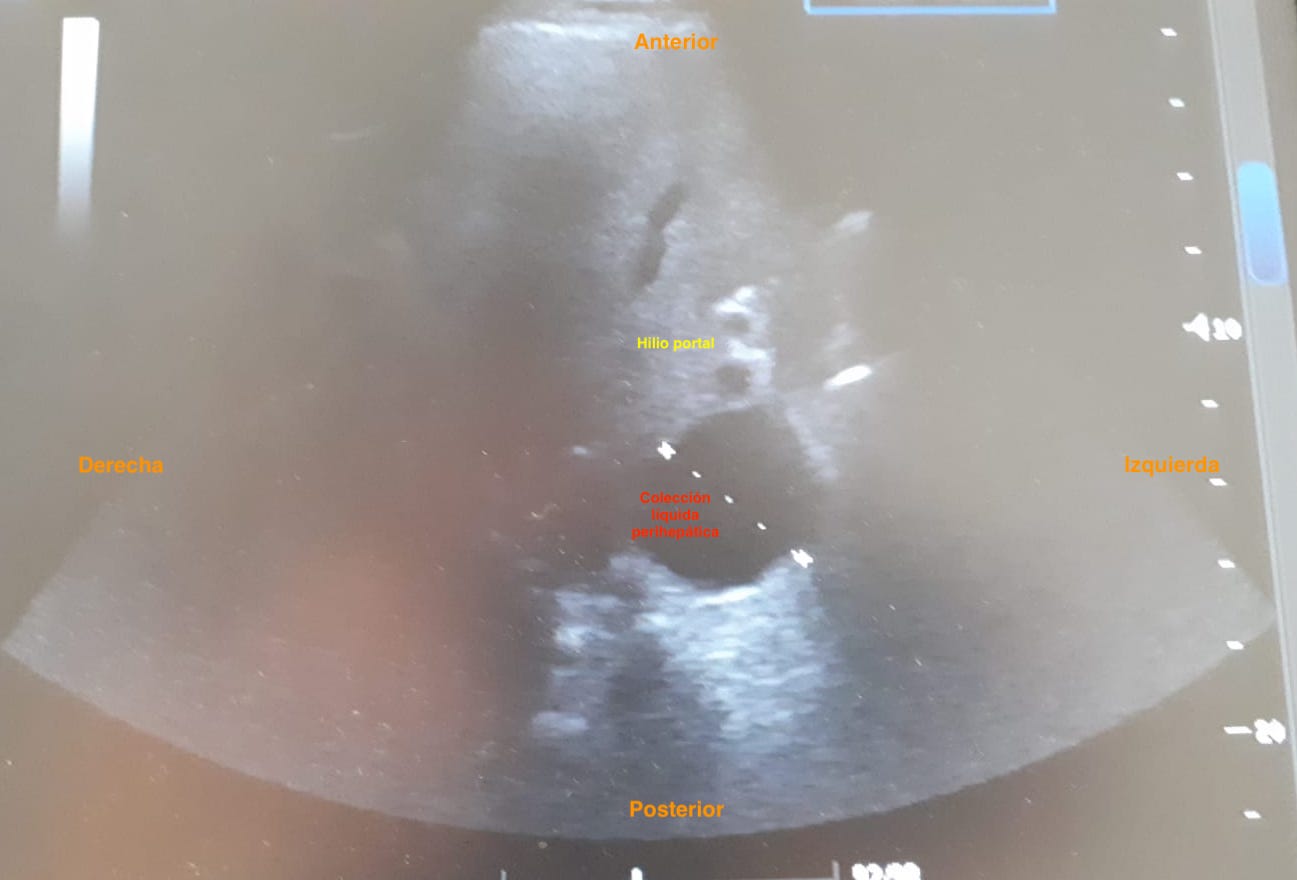

Hallazgos ecográficos

Colección líquida bien definida localizada posteriormente a lóbulo hepático izquierdo, adyacente a vena cava. Líquido peritoneal en fosa ilíaca derecha y flanco derecho, a nivel inferolateral de RD, espacio de Morrison conservado. Cantidad moderada de líquido en la pelvis.

• ECO ABD: Persistencia liquido perihepático.